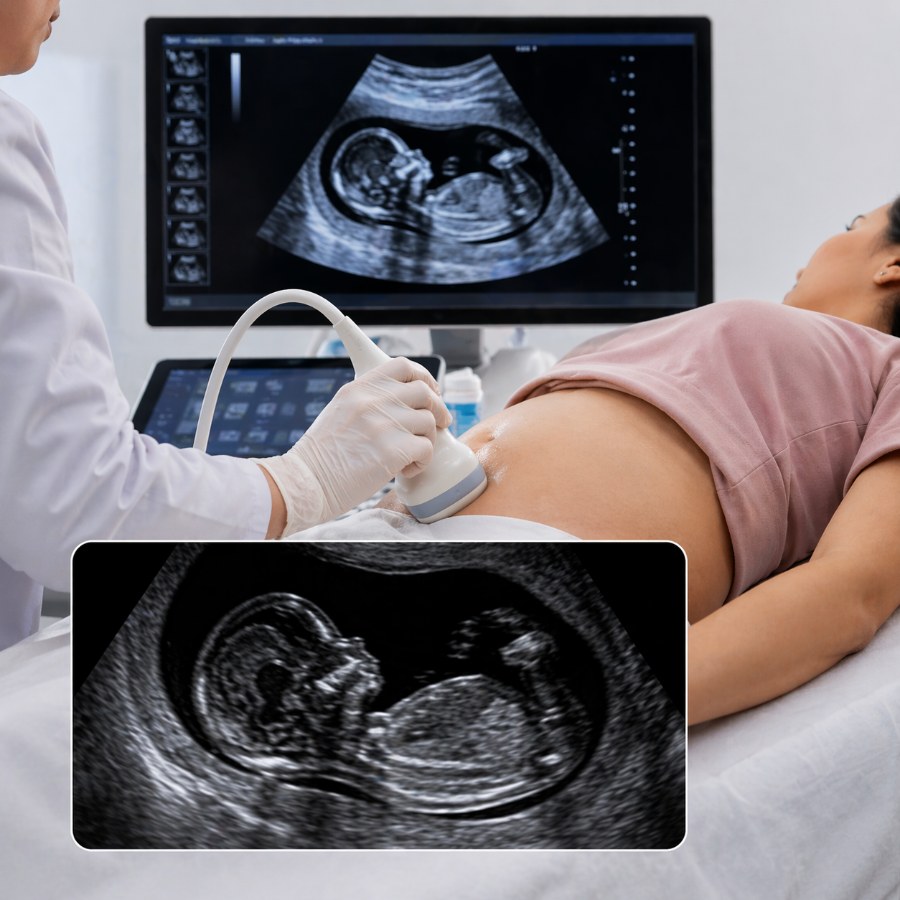

An NT NB Scan is an important pregnancy ultrasound performed during the first trimester to assess the baby’s early development and screen for chromosomal abnormalities. It includes:

• NT (Nuchal Translucency) – measures fluid behind the baby’s neck

• NB (Nasal Bone) – checks presence and development of the baby’s nasal bone

This scan helps identify the risk of conditions such as Down syndrome and other fetal abnormalities.

The NT NB Scan is usually performed between 11 weeks to 13 weeks 6 days of pregnancy. It is a safe ultrasound test that helps evaluate fetal growth and early markers for genetic conditions.